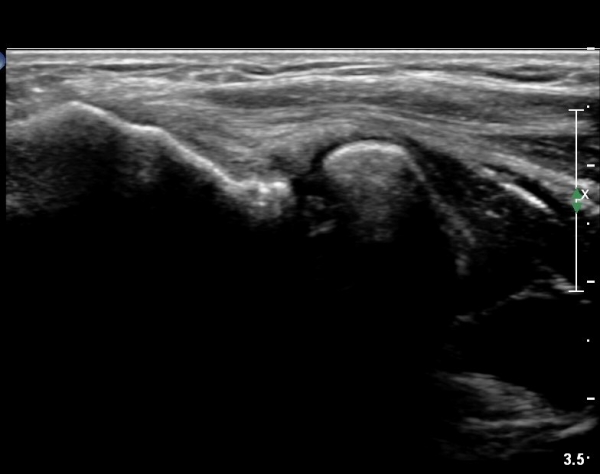

¿Ü»ó°ú¿¡¼­ ¼Õ¸ñ ½ÅÀü°Ç ´ÜµÎ Á¾´Ü¸é°Ë»ç¿¡¼­ ƯÀÌ ¼Ò°ßÀ» º¸ÀÌÁö ¾Ê´Â´Ù(»çÁø 1, 2)

¿ä°ñµÎ ºÎÀ§ ÆÈ²ÞÄ¡ ¾Õ, ¿ÜÃø Ⱦ´Ü¸é°Ë»ç¿¡¼­ Èİñ°£ ½Å°æ ³»Ãø, ¿ä°ñµÎ Ç¥Ãþ¿¡¼­

ÀÛÀº ³¶Á¾ÀÌ °üÂûµÈ´Ù(»çÁø 3)